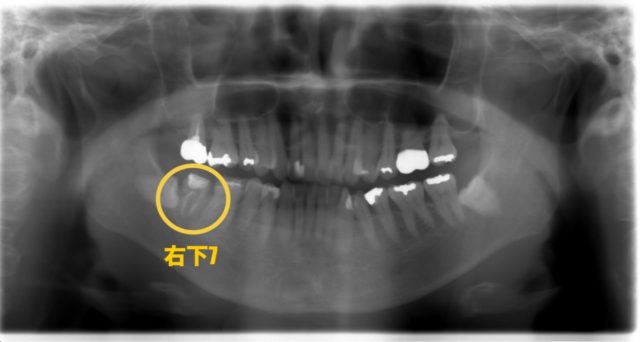

まずはパノラマ写真と口腔内写真をご覧下さい。

今回の部位は右下7番です。他院にて根管治療中ですが、痛みが治まらず当院を来院されました。なので仮蓋が詰められた状態です。

歯茎が白くなっている部分は膿の出口です。かなり大きいですね、、